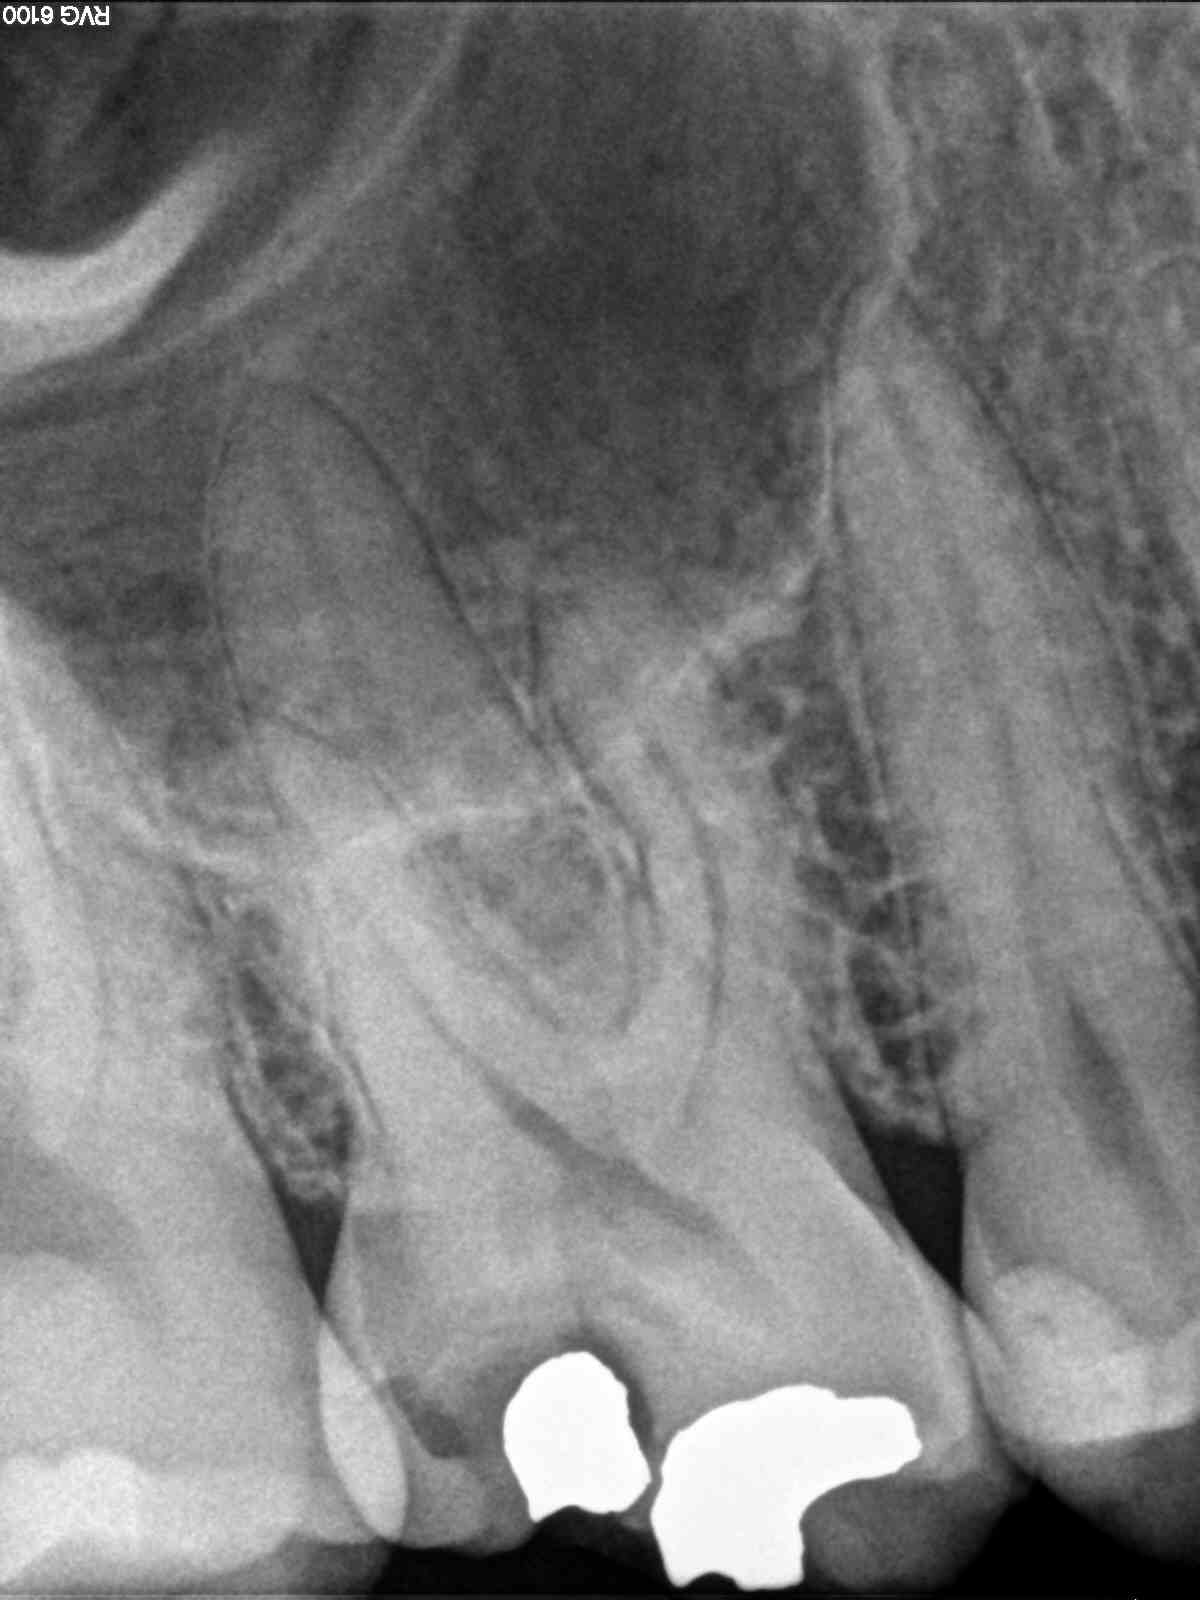

C) Por último, no encontramos un 1.6 con otra pulpitis irreversible.

C)